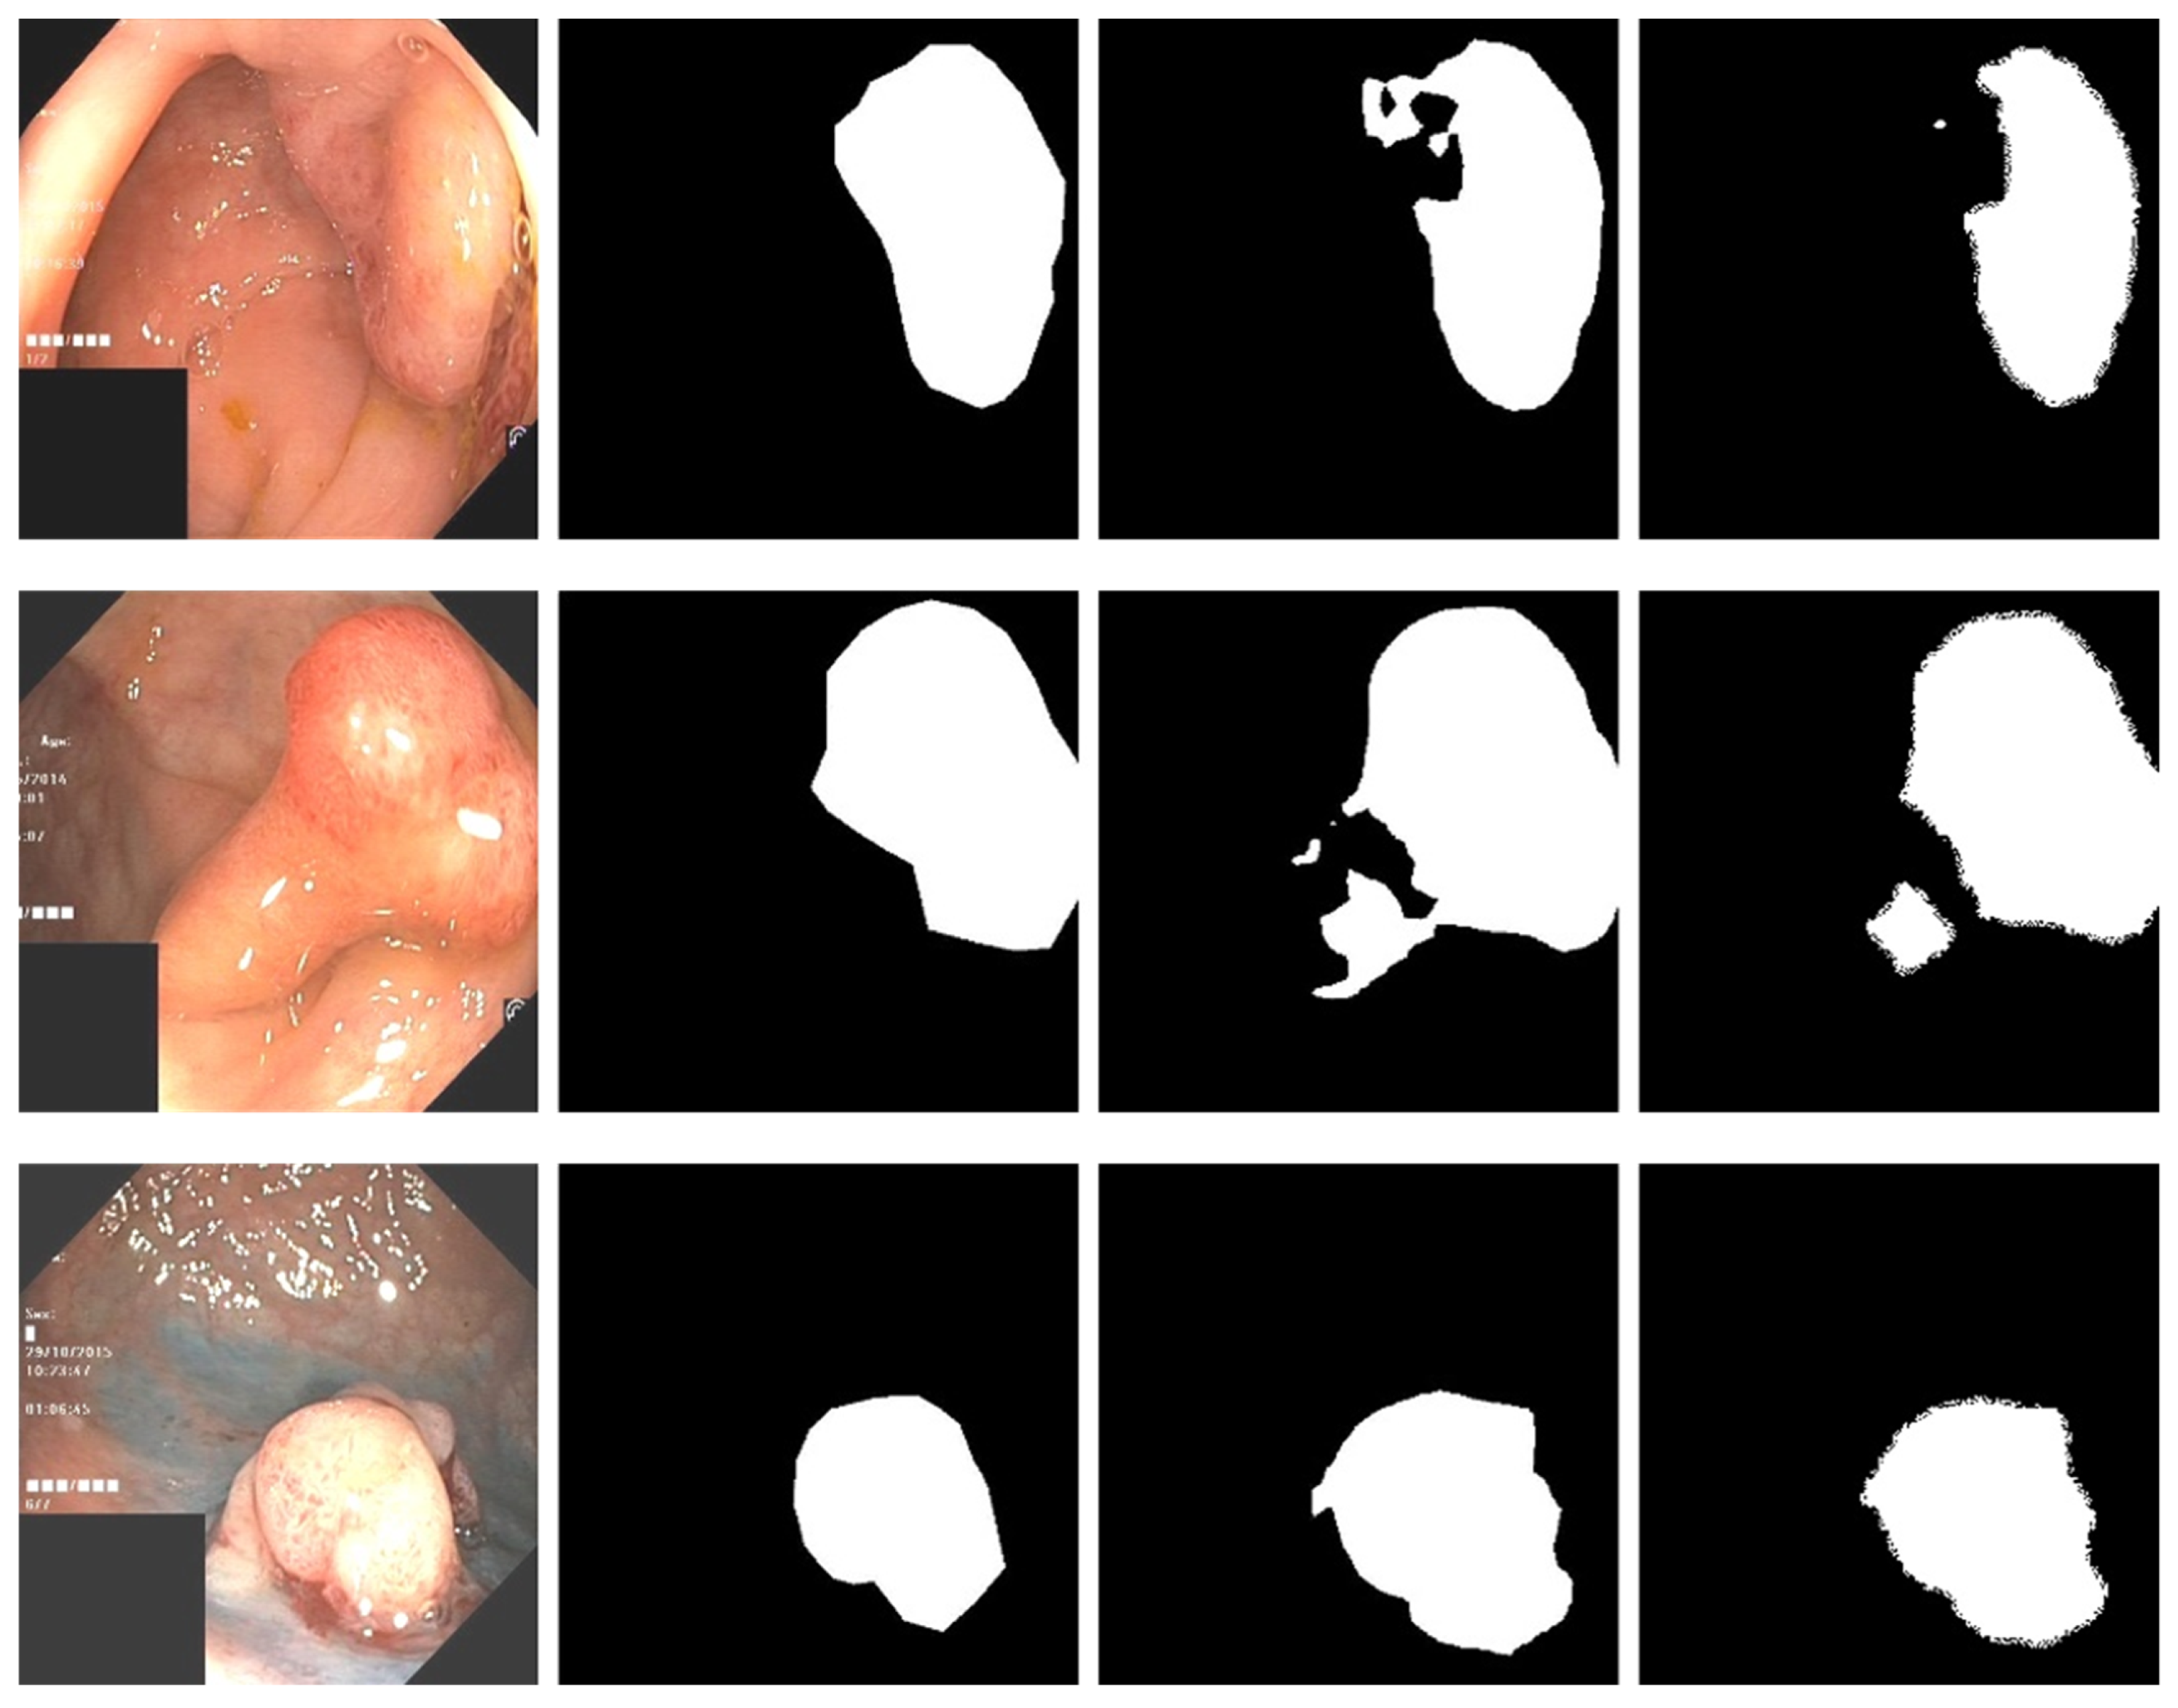

3.1. Data Preprocessing

3.4. Experimental Results